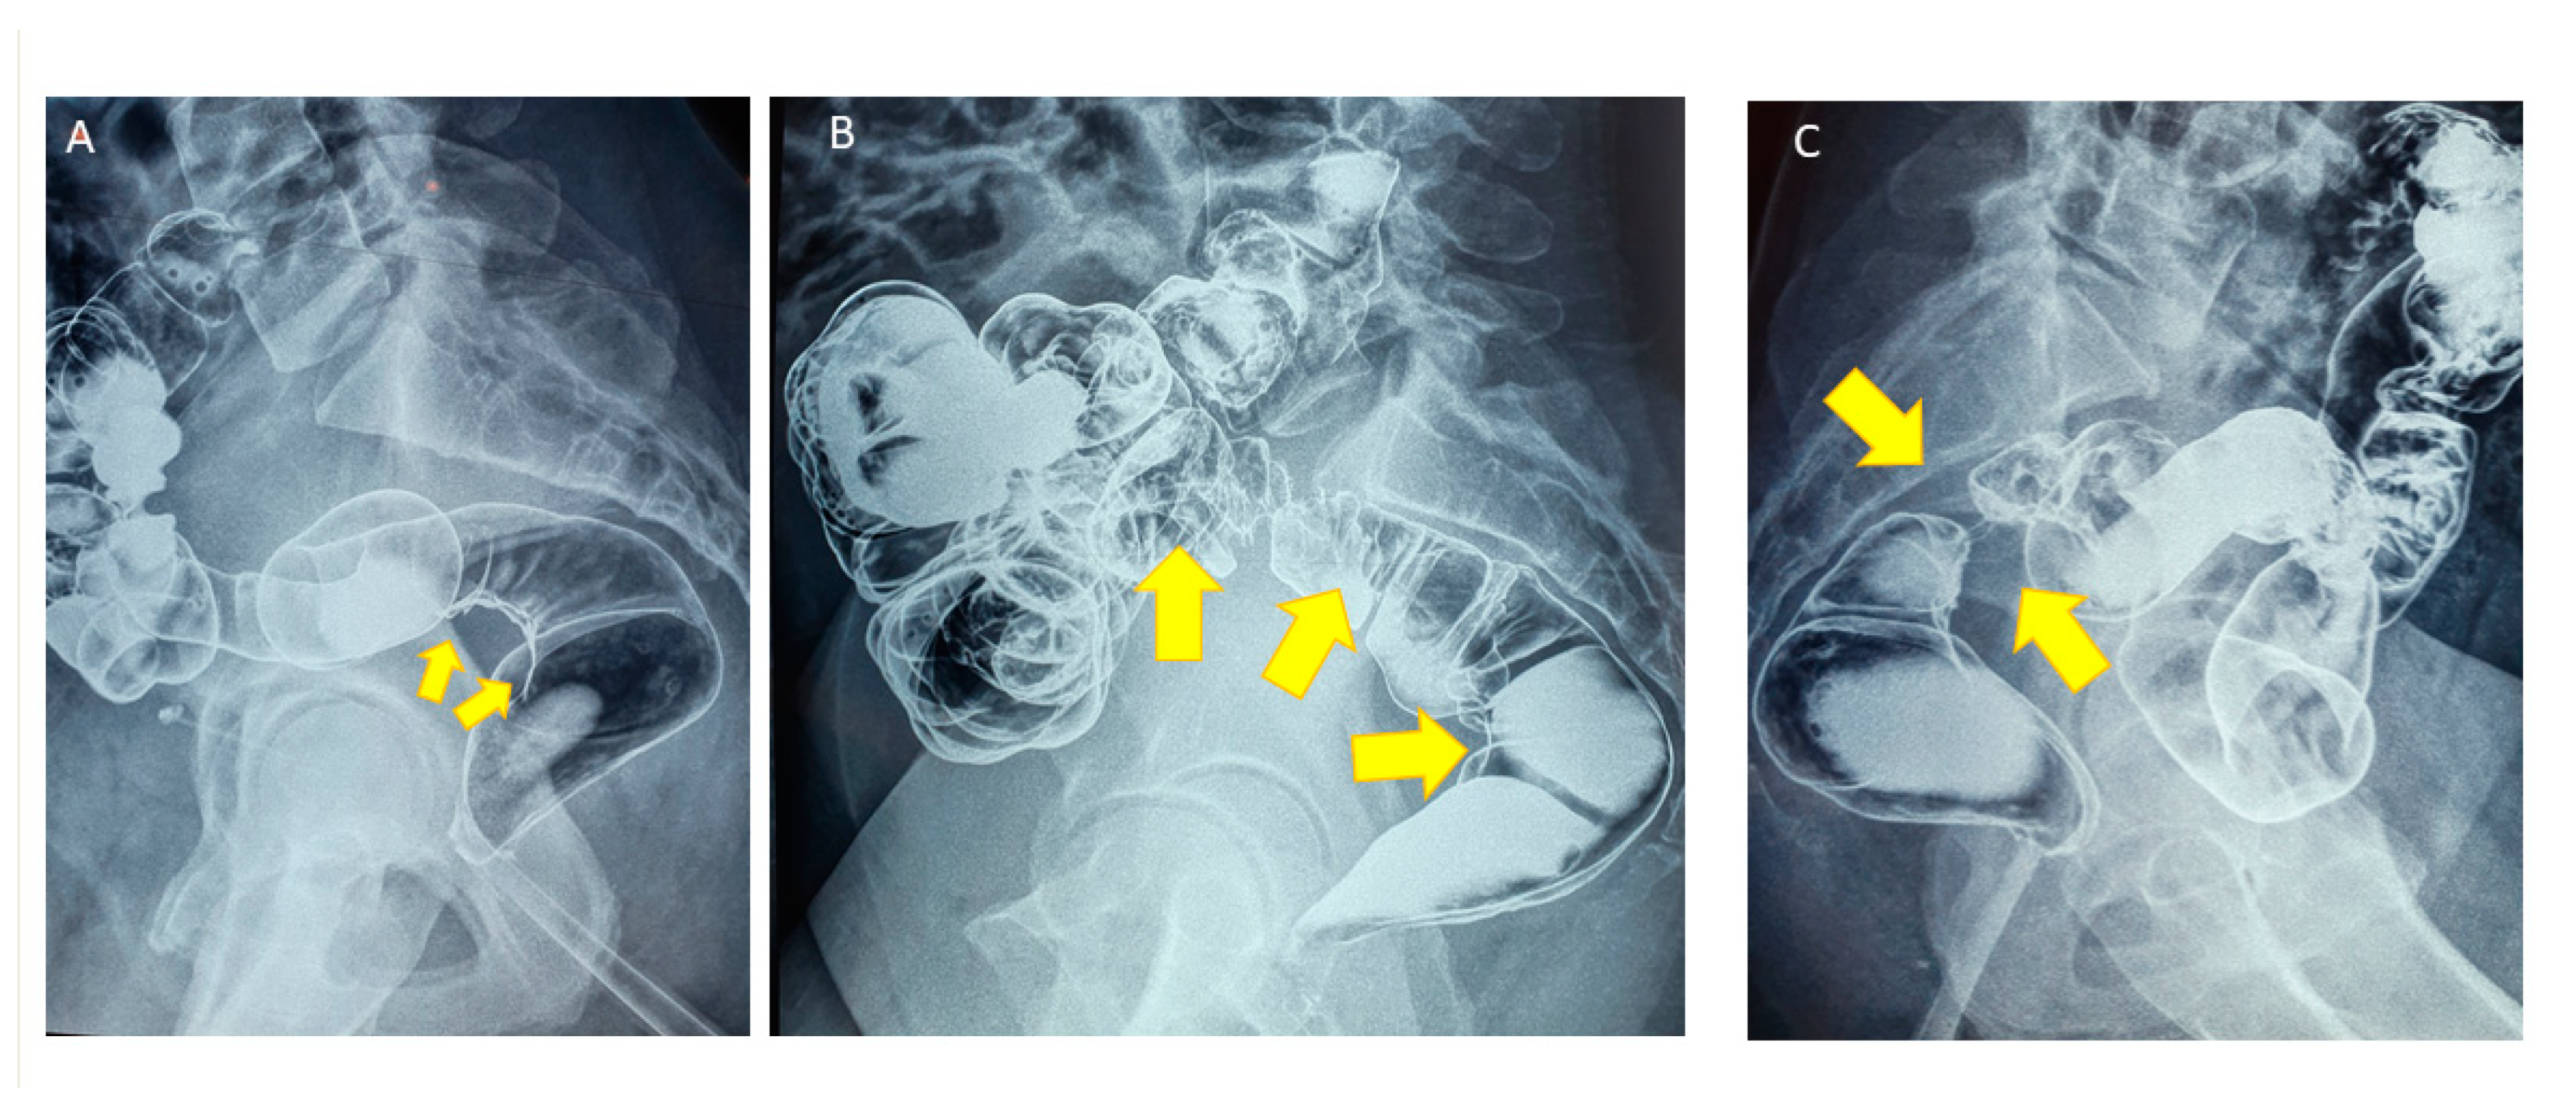

- Jaramillo-Cardoso, A.; Shenoy-Bhangle, A.S.; VanBuren, W.M.; Schiappacasse, G.; Menias, C.O.; Mortele, K.J. Imaging of gastrointestinal endometriosis: What the radiologist should know. Abdom. Radiol. 2020, 45, 1694–1710. [Google Scholar] [CrossRef]

- Biscaldi, E.; Barra, F.; Leone Roberti Maggiore, U.; Ferrero, S. Other imaging techniques: Double-contrast barium enema, endoscopic ultrasonography, multidetector CT enema, and computed tomography colonoscopy. Best Pract. Res. Clin. Obstet. Gynaecol. 2021, 71, 64–77. [Google Scholar] [CrossRef] [PubMed]

- Anaf, V.; El Nakadi, I.; De Moor, V.; Coppens, E.; Zaeleman, M.; Noel, J.C. Anatomic significance of a positive barium enema in deep infiltrating endometriosis of the large bowel. World J. Surg. 2009, 33, 822–827. [Google Scholar] [CrossRef]

- Abrão, M.S.; Podgaec, S.; Dias, J.A., Jr.; Averbach, M.; Silva, L.F.; Marino de Carvalho, F. Endometriosis lesions that compromise the rectum deeper than the inner muscularis layer have more than 40% of the circumference of the rectum affected by the disease. J. Minim. Invasive Gynecol. 2008, 15, 280–285. [Google Scholar] [CrossRef] [PubMed]

- Goncalves, M.O.; Podgaec, S.; Dias, J.A., Jr.; Gonzalez, M.; Abrao, M.S. Transvaginal ultrasonography with bowel preparation is able to predict the number of lesions and rectosigmoid layers affected in cases of deep endometriosis, defining surgical strategy. Hum. Reprod. 2010, 25, 665–671. [Google Scholar] [CrossRef] [PubMed]